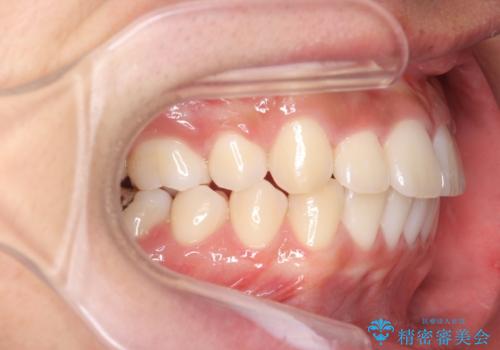

抜歯矯正の長期予後(術後8年目)

- ワイヤー矯正による治療後7年以上経過した患者様です。当時上の小臼歯を2本抜歯しています。

10代で矯正治療を行い、現在20代になられています。

矯正後8年目になりますが、並びも綺麗に保持でき、また上下の歯がさらにしっかり咬んできているのがわかります。

定期的にメンテナンスにきていただき、特に歯の健康状態にも問題がありません。

下は歯につけるタイプのワイヤーを貼っています。

上は取り外し式の装置を就寝時使っていただいています。